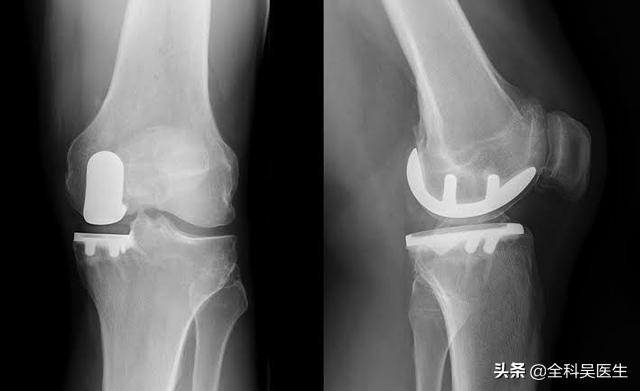

関節の症状が特に重く、患者さんが明らかな関節の変形普通に歩くことができず、500メートル以上歩くと関節に著しい痛みがあり、安静時や睡眠時の痛みがひどい場合は、人工関節置換術の適応となります。人工膝関節置換術が、患者を完全に救う唯一の方法かもしれない。。

9.人工膝関節置換術変形性膝関節症が明らかに関節の変形を引き起こし、患者の生活に深刻な影響を及ぼすようであれば、人工膝関節置換術によって患者の問題を完全に解決しなければなりません。

遅発性:激しい痛みを和らげるための人工関節

病気の後期になると、患者の軟骨はほとんどすり減ります。軟骨のクッションがなければ、骨と骨が直接こすれ合うことになる。この段階では、人工関節に置き換えるか、関節固定術を行うかしか選択肢はありませんが、術後の患者の運動能力に深刻な影響を及ぼす可能性があるため、ほとんど行われません。